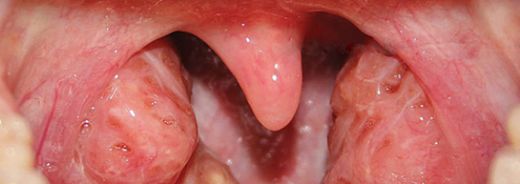

Cevap yazSol Bademcik Çürümeleri Belirtileri

Sol bademcik çürümeleri genellikle yutkunma zorluğu, boğazda tahriş, ağrı ve yüksek ateş gibi belirtilerle kendini gösterir. Bu durum, bademcik iltihabı veya diğer enfeksiyonların bir sonucu olabilir.

Sol bademcik şişmesi yaşadım ve gerçekten rahatsız edici bir durum. Boğazımda ağrı ve yutkunma güçlüğü ile birlikte beyaz lekeler oluştu. Tedavi için doktora başvurdum. Tek taraflı bademcik şişmesi doktor sitesinde de belirttiği gibi önemli bir durum, dikkat edilmesi lazım.

Alpartur, yaşadığın bu durum gerçekten de rahatsız edici olabilir. Boğazdaki ağrı ve yutkunma güçlüğü, günlük yaşamı olumsuz etkileyebilir. Beyaz lekelerin varlığı, enfeksiyon belirtilerine işaret edebilir ve bu nedenle doktora başvurman çok önemli bir adım.